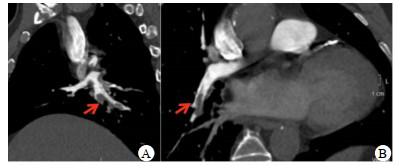

1 资料与方法患者,男性,74岁,因“冠脉介入术后即刻胸闷伴呼吸困难”,于2020年12月29日入急诊监护室。入监护室前经桡动脉行冠脉造影示右冠(right coronary artery, RCA)慢性闭塞病变,左前降支(left anterior descending artery, LAD)近中段狭窄80%,左回旋支(left circumflex artery, LCX)支架内狭窄80%。开通RCA闭塞病变,植入2枚支架(图 1 A~D),手术过程顺利。术后即刻突发胸闷胸痛,呼吸困难,送至监护室,心电图提示前壁V1~V5导联ST段抬高0.4 mV(图 2)。血压105/60 mmHg(1 mmHg=0.133 kPa),心率80次/min,呼吸频率30次/min,氧饱和度88%(空气氧)。考虑急性前壁心肌梗死,立即行急诊冠脉造影,经桡动脉,示LAD中段狭窄80%,但较之前造影未见进展,TIMI Ⅲ级血流;LCX支架处狭窄80%,血流TIMI Ⅲ级;RCA支架通畅,膨胀良好,血流TIMI Ⅲ级(图 1 E~G)。在LAD近中段植入两枚支架,并于LCX支架狭窄处行球囊扩张(图 1 H、I),术中ACT为230~270 s。

| A~D为第一次冠脉造影和治疗:A~C为患者入监护室前第一次行冠脉造影LAD和LCX重度狭窄,RCA闭塞;D为RCA治疗植入支架后血流通畅;E~G为再次胸痛后造影:E~F为患者胸痛后再次急诊冠脉造影LAD及LCX血流通畅,未见血栓,狭窄较前无变化;G为复查RCA造影示支架通畅;H~I为二次治疗后影像:H为LAD支架植入后解除狭窄;I为LCX球囊扩张后解除狭窄 图 1 患者冠脉造影 |